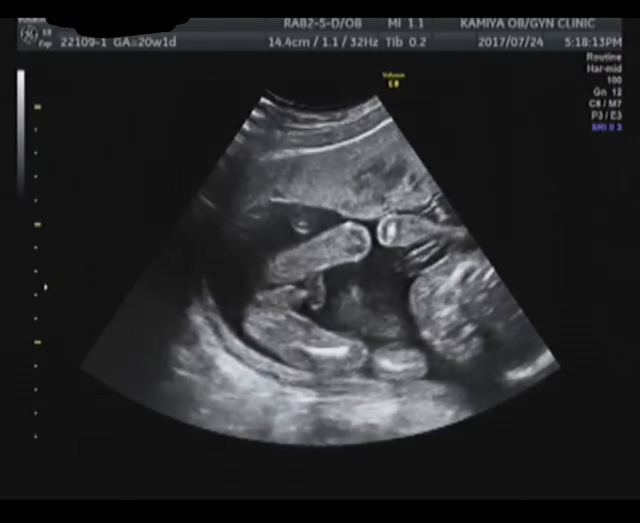

15週2日(15w2d・男の子)|ぎふっこみかん さん(29歳)

エコー写真撮影時のエピソード:

初めて性別が分かった日、両足をバーンと大胆に広げて見せてくれました。

まるで見てと言わんばかりに赤ちゃんの向きもエコーで撮りやすい向きだったみたいで、旦那さんと大笑い。先生からも自己主張強いねーの一言。とても印象に残ってます。